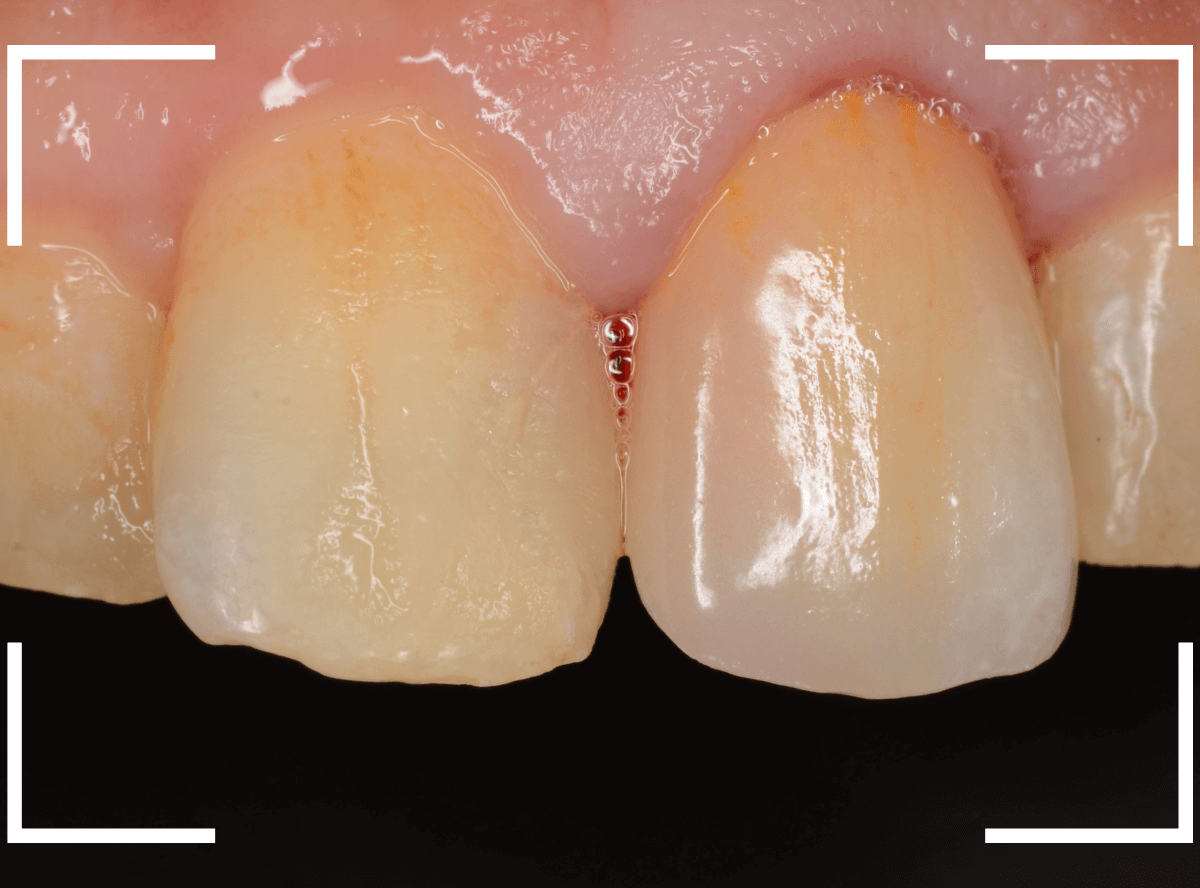

お口の中でsetしたところです。

お口の中に入った状態のビフォーアフターです。

見た目の印象も大きく変わったかと思います。

また、以前のさし歯に比べて、舌触りがとてもよくなったとの感想もいただきました。

恥ずかしながら、私自身もセラミックのさし歯をいれていますが、同じ感想でした。

舌触りが滑らか=汚れがたまりづらく、虫歯や歯周病になりづらい、という健康上のメリットも大きいです。